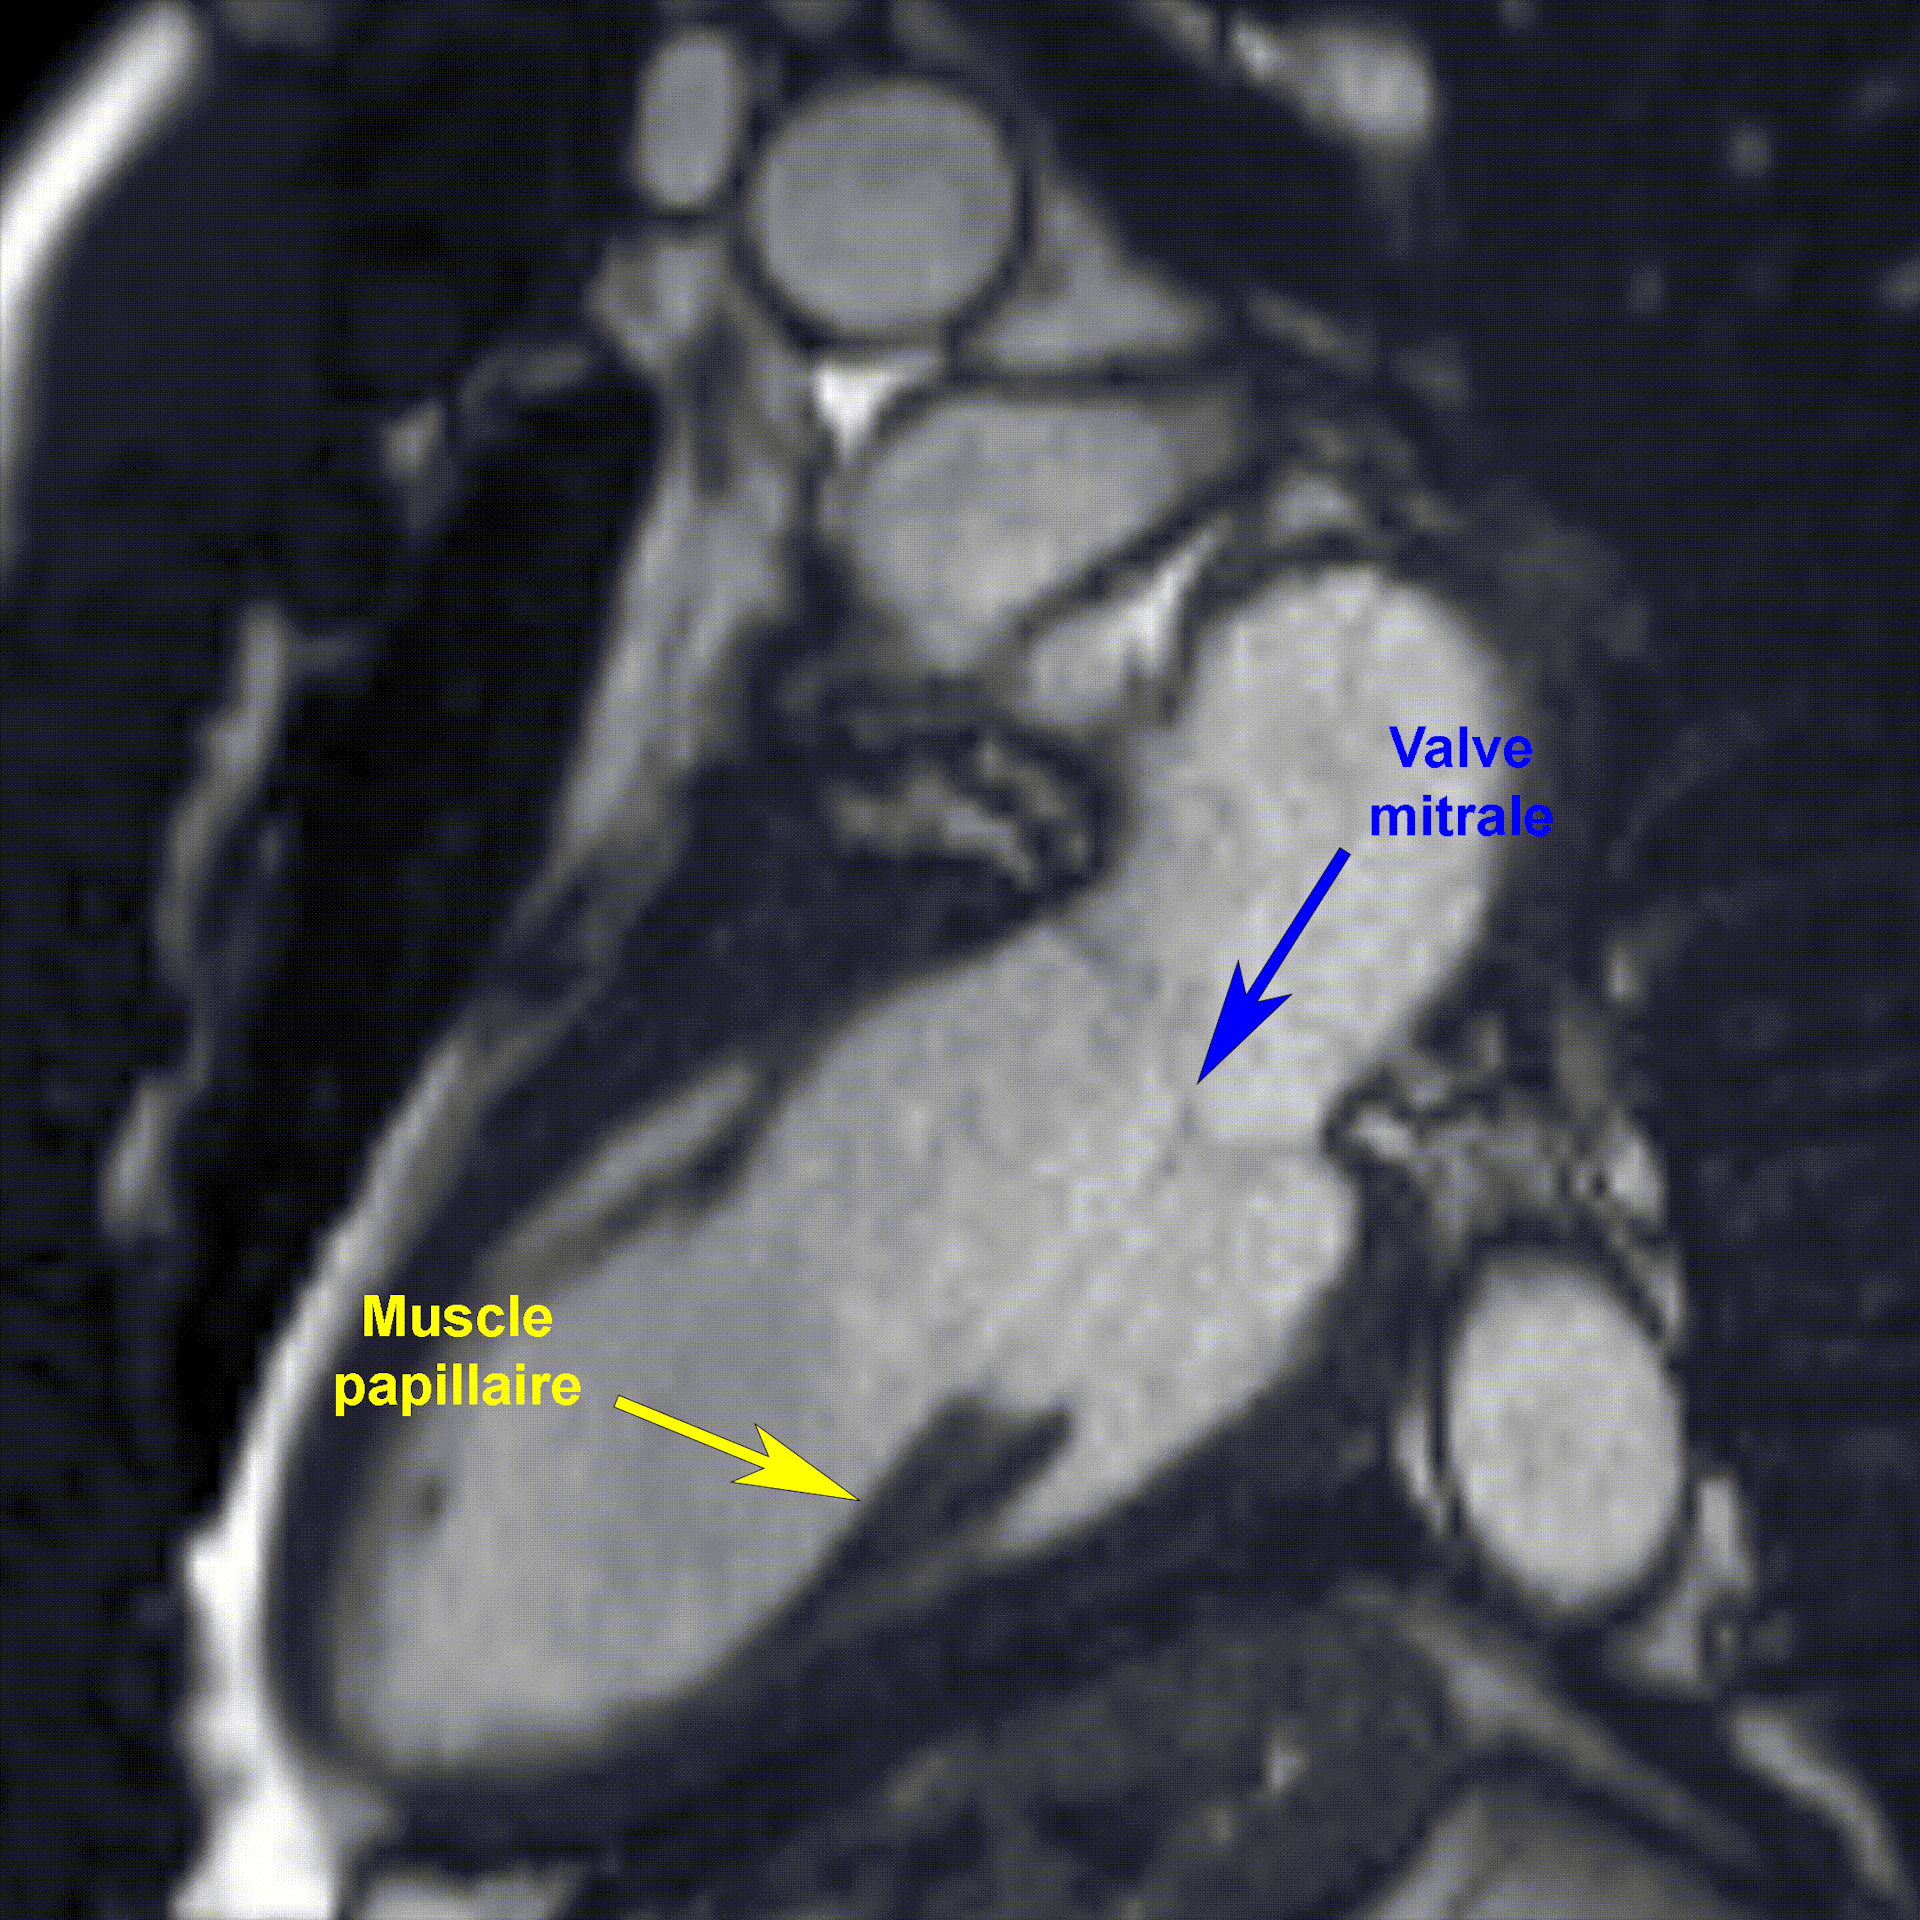

La mission principale du cœur est de faire circuler le sang à travers les poumons et le corps. Pour cela, il est composé de quatre cavités se contractant à un rythme régulier. Des valves jouent le rôle de clapet antiretour et empêchent le sang de circuler dans le mauvais sens.

Pour accomplir leur fonction, elles reçoivent l’aide de petites structures musculaires, qui représentent moins de 10 % de la masse totale du cœur : les muscles papillaires. Ces derniers évitent que, lorsque le cœur se contracte, les valves ne se retournent comme un parapluie par grand vent. C’est d’ailleurs précisément ce qui se passe en cas d’insuffisance mitrale, une pathologie qui touche des millions de personnes – principalement âgées – dans le monde.

Université Libre de Bruxelles, Fourni par l’auteur

Pour combler cette lacune, nous avons utilisé l’imagerie par résonance magnétique (IRM) afin de mesurer précisément la masse de ces petits muscles chez des astronautes assignés à des missions spatiales de longue durée (de six à douze mois) à bord de l’ISS. Les mesures avaient lieu dans une période de quarante-cinq à soixante jours avant le décollage et environ une semaine après leur retour sur Terre.

Nos résultats ont mis en évidence une réduction moyenne de 14 % de la masse des muscles papillaires après le vol spatial. Cette atrophie sélective, combinée à la sphéricité accrue du cœur observée en impesanteur ainsi qu’à une augmentation de 6 % du diamètre de la valve mitrale (située entre l’oreillette gauche et le ventricule gauche), crée des conditions anatomiques qui pourraient théoriquement favoriser un manque d’étanchéité de ladite valve.